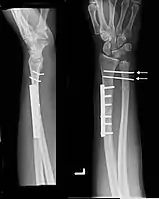

Galeazzi fracture after surgical fixation